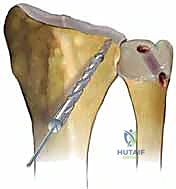

* Ulnar Tunnel Preparation:

* Elevate the ulnar flap of the DRUJ capsulotomy to expose the ulnar head and neck, again, being scrupulous not to injure the ECU tendon sheath.

* Now, we need to access the ulnar fovea. Flex the wrist and pronate the forearm to help retract the TFCC remnant and provide better visualization.

* The ulnar bone tunnel will travel from the ulnar fovea to exit on the lateral ulnar neck, just volar to the ECU tendon.

* Retrograde Technique (Preferred): Pass a guidewire retrograde from the ulnar fovea (identified by its characteristic depression) to exit on the lateral ulnar neck. Confirm this position with fluoroscopy.

* Antegrade Technique (Alternative): If exposure of the fovea is inadequate despite wrist flexion, you may create the tunnel antegrade from the lateral ulnar neck to the fovea. If using this approach, be extremely careful to protect any remaining TFCC tissue and the ulnar carpus with a blunt probe or elevator as the drill exits.

* Confirm guidewire position with fluoroscopy.

* Drill the ulnar tunnel. Remember, this tunnel must accommodate both limbs of the tendon graft, so you may need to enlarge it slightly with a standard drill bit after the initial 3.5mm cannulated drill.